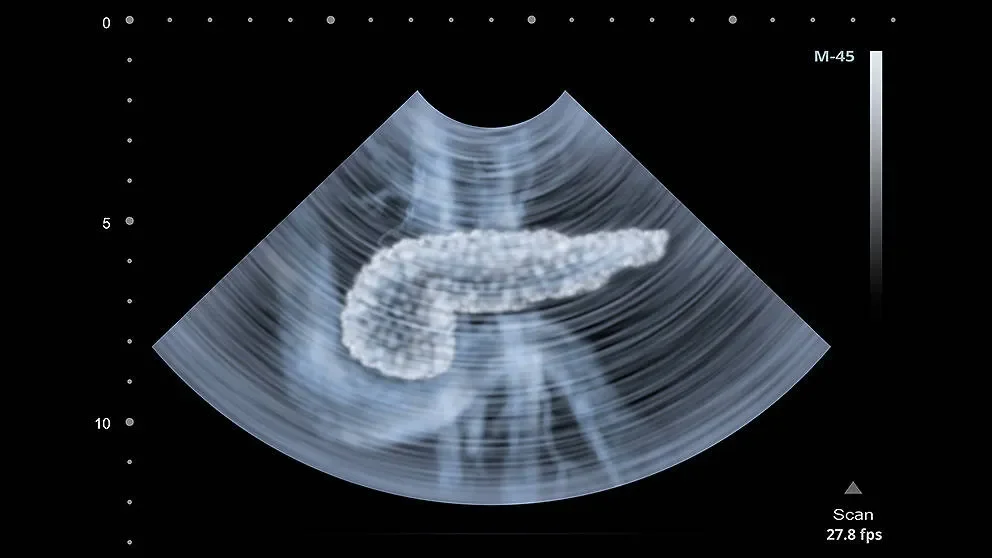

It’s well known that pancreatic islets of Langerhans contain cells that secrete hormones vital to maintaining glucose homeostasis, including insulin. But the cells comprising the islets are of different types and perform different, complementary functions. Understanding their discrete roles in both normal function and in disease, such as type 2 diabetes, is crucial to developing effective therapies. Unfortunately, conventional sorting techniques have not been sufficient to isolate the individual islet cell types, making it impossible to analyze each one’s gene expression program and its potential contribution to dysfunction.

To overcome this limitation, a team led by JAX Assistant Professor Michael Stitzel, Ph.D., isolated single cells from the pancreatic islets of both non-diabetic and type 2 diabetic subjects to obtain transcriptomes for each cell. As reported online inGenome Research on November 18, the cells yielded distinct signatures that allowed the researchers to identify 239 alpha, 264 beta, 25 delta and 18 pancreatic polypeptide (PP)/gamma cells. It has been particularly difficult to assess changes in the less common cell types, and of the 24 genes exhibiting differential expression between diabetic and non-diabetic delta cells, ~90% had not been detected in whole islet or non-stratified islet cell transcriptomes. Further, the data suggest that delta cells may perform key roles as integrators and coordinators of central and peripheral metabolic signals.